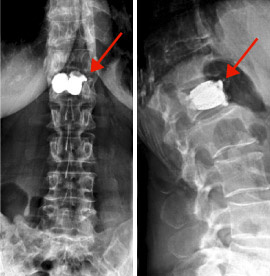

hirslanden-wirbelsaeuleneingriffe-beim-alternden-menschen-3

Abb. 3

Wirbelkörperverstärkung durch Zement

Wirbelkompressionsfrakturen

Bei den durch Osteoporose verursachten Wirbelkompressionsfrakturen treten meist ausgeprägte Rückenschmerzen auf, eventuell begleitet von ausstrahlenden Schmerzen in die Beine. Viele dieser Knochenbrüche lassen sich mit Schmerzmittel behandeln, um die Heilungsphase bis zur Verknöcherung des Bruches zu überbrücken.

Ein Teil der Frakturen zeigt jedoch eine zunehmende Absackung (Einsinterung), was eine Verkrümmung der Wirbelsäule mit sich zieht, vor allem in der seitlichen Ebene (Kyphose). Dies führt wiederum zu einer vermehrten Belastung der durch die Osteoporose geschwächten Wirbelkörper und damit zu neuen Frakturen. Die Wirbelsäulenverkrümmung kann zu einer Einengung der Bauchorgane und der Lunge und so letztlich zum Tode führen.

Die Zementauffüllung (Vertebroplastik, Kyphoplastik) der Wirbel ist eine minimalinvasive (gewebeschonende) Behandlungsmethode dieser Frakturen, die meist bei älteren Menschen mit zusätzlichen medizinischen Problemen angewendet wird. Hierfür wird eine Kanüle durch die Haut in den Wirbelkörper vorgeschoben, ohne dass die Wirbelsäule durch ein offenes chirurgisches Vorgehen freigelegt werden muss (Abb. 3).